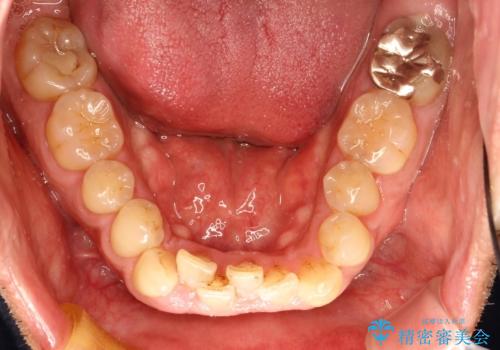

インビザライン invisalign ガタつきを治すマウスピース矯正

- 非抜歯・上顎臼歯遠心移動によるマウスピース矯正を計画した。

ガタつきを取り除くだけであれば非常に簡潔であるマウスピース矯正ですが、奥歯の位置関係の是正や、垂直的な歯の位置のコントロールなどが計画に含まれる場合、治療が難しくなってきます。